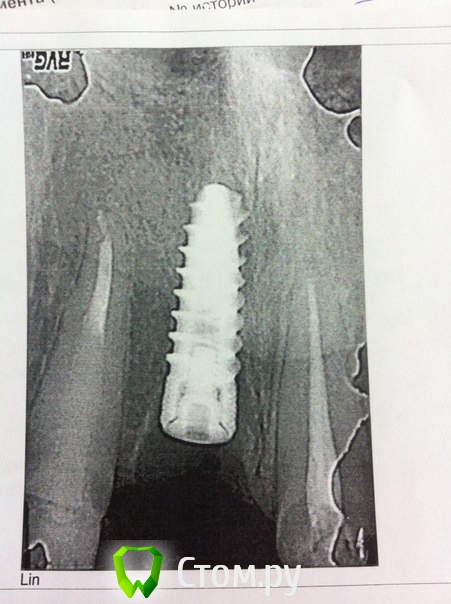

Dr.noEvil Опубликовано 10 апреля, 2014 Поделиться Опубликовано 10 апреля, 2014 Пациентка 35 лет, улыбка бело-розовая, ранее была конструкция 11-12 МК мостовидный протез, зубы не витальные, 11 культевая вкладка, 21-22 МК мостовидный протез, зубы не витальные. Обратилась в клинику с целью поменять коронки, зуб 11- прелом корня на уровне 1/4 коронально. Сняли коронки, сделали временный протез 12-21-23. Удалил зуб 11, дефект кости вестибулярно, ниже на 2,5 мм в сравнении с апроксимальными стенками. Установлен имплантат мисс7 13мм 4,2мм, 35 Н. Пластики не было сделано( причины обсуждать смысла уже нет, выкладываю уже сложившуюся ситуацию). В итоге ожидает ортопедический ужас! Биотип слизистой между средним и тонким. Подскажите как поступить в этой ситуации, имплантат установлен 9 апреля. Возможно ли выкруить 3 витка и сделать пластику? Ссылка на комментарий

Maxfac Опубликовано 11 апреля, 2014 Поделиться Опубликовано 11 апреля, 2014 Уважаемые коллеги,я тоже начинающий имплантолог и очень прошу разъяснить мне в чём конкретно тут проблема: в отсутствие изначального нкр или глубоко поставленный имплант?Заранее спасибо.Неправильно спозиционированный имплантат в эстетически значимой зоне. Ссылка на комментарий

Maxfac Опубликовано 12 апреля, 2014 Поделиться Опубликовано 12 апреля, 2014 (изменено) То есть глубоко по отношению к соседним зубам?Глубоко. Плюс отсутствие нкр, скорее всего, приведет к избыточному ремоделированию в этой зоне. Короче, косяк. Изменено 12 апреля, 2014 пользователем Maxfac Ссылка на комментарий